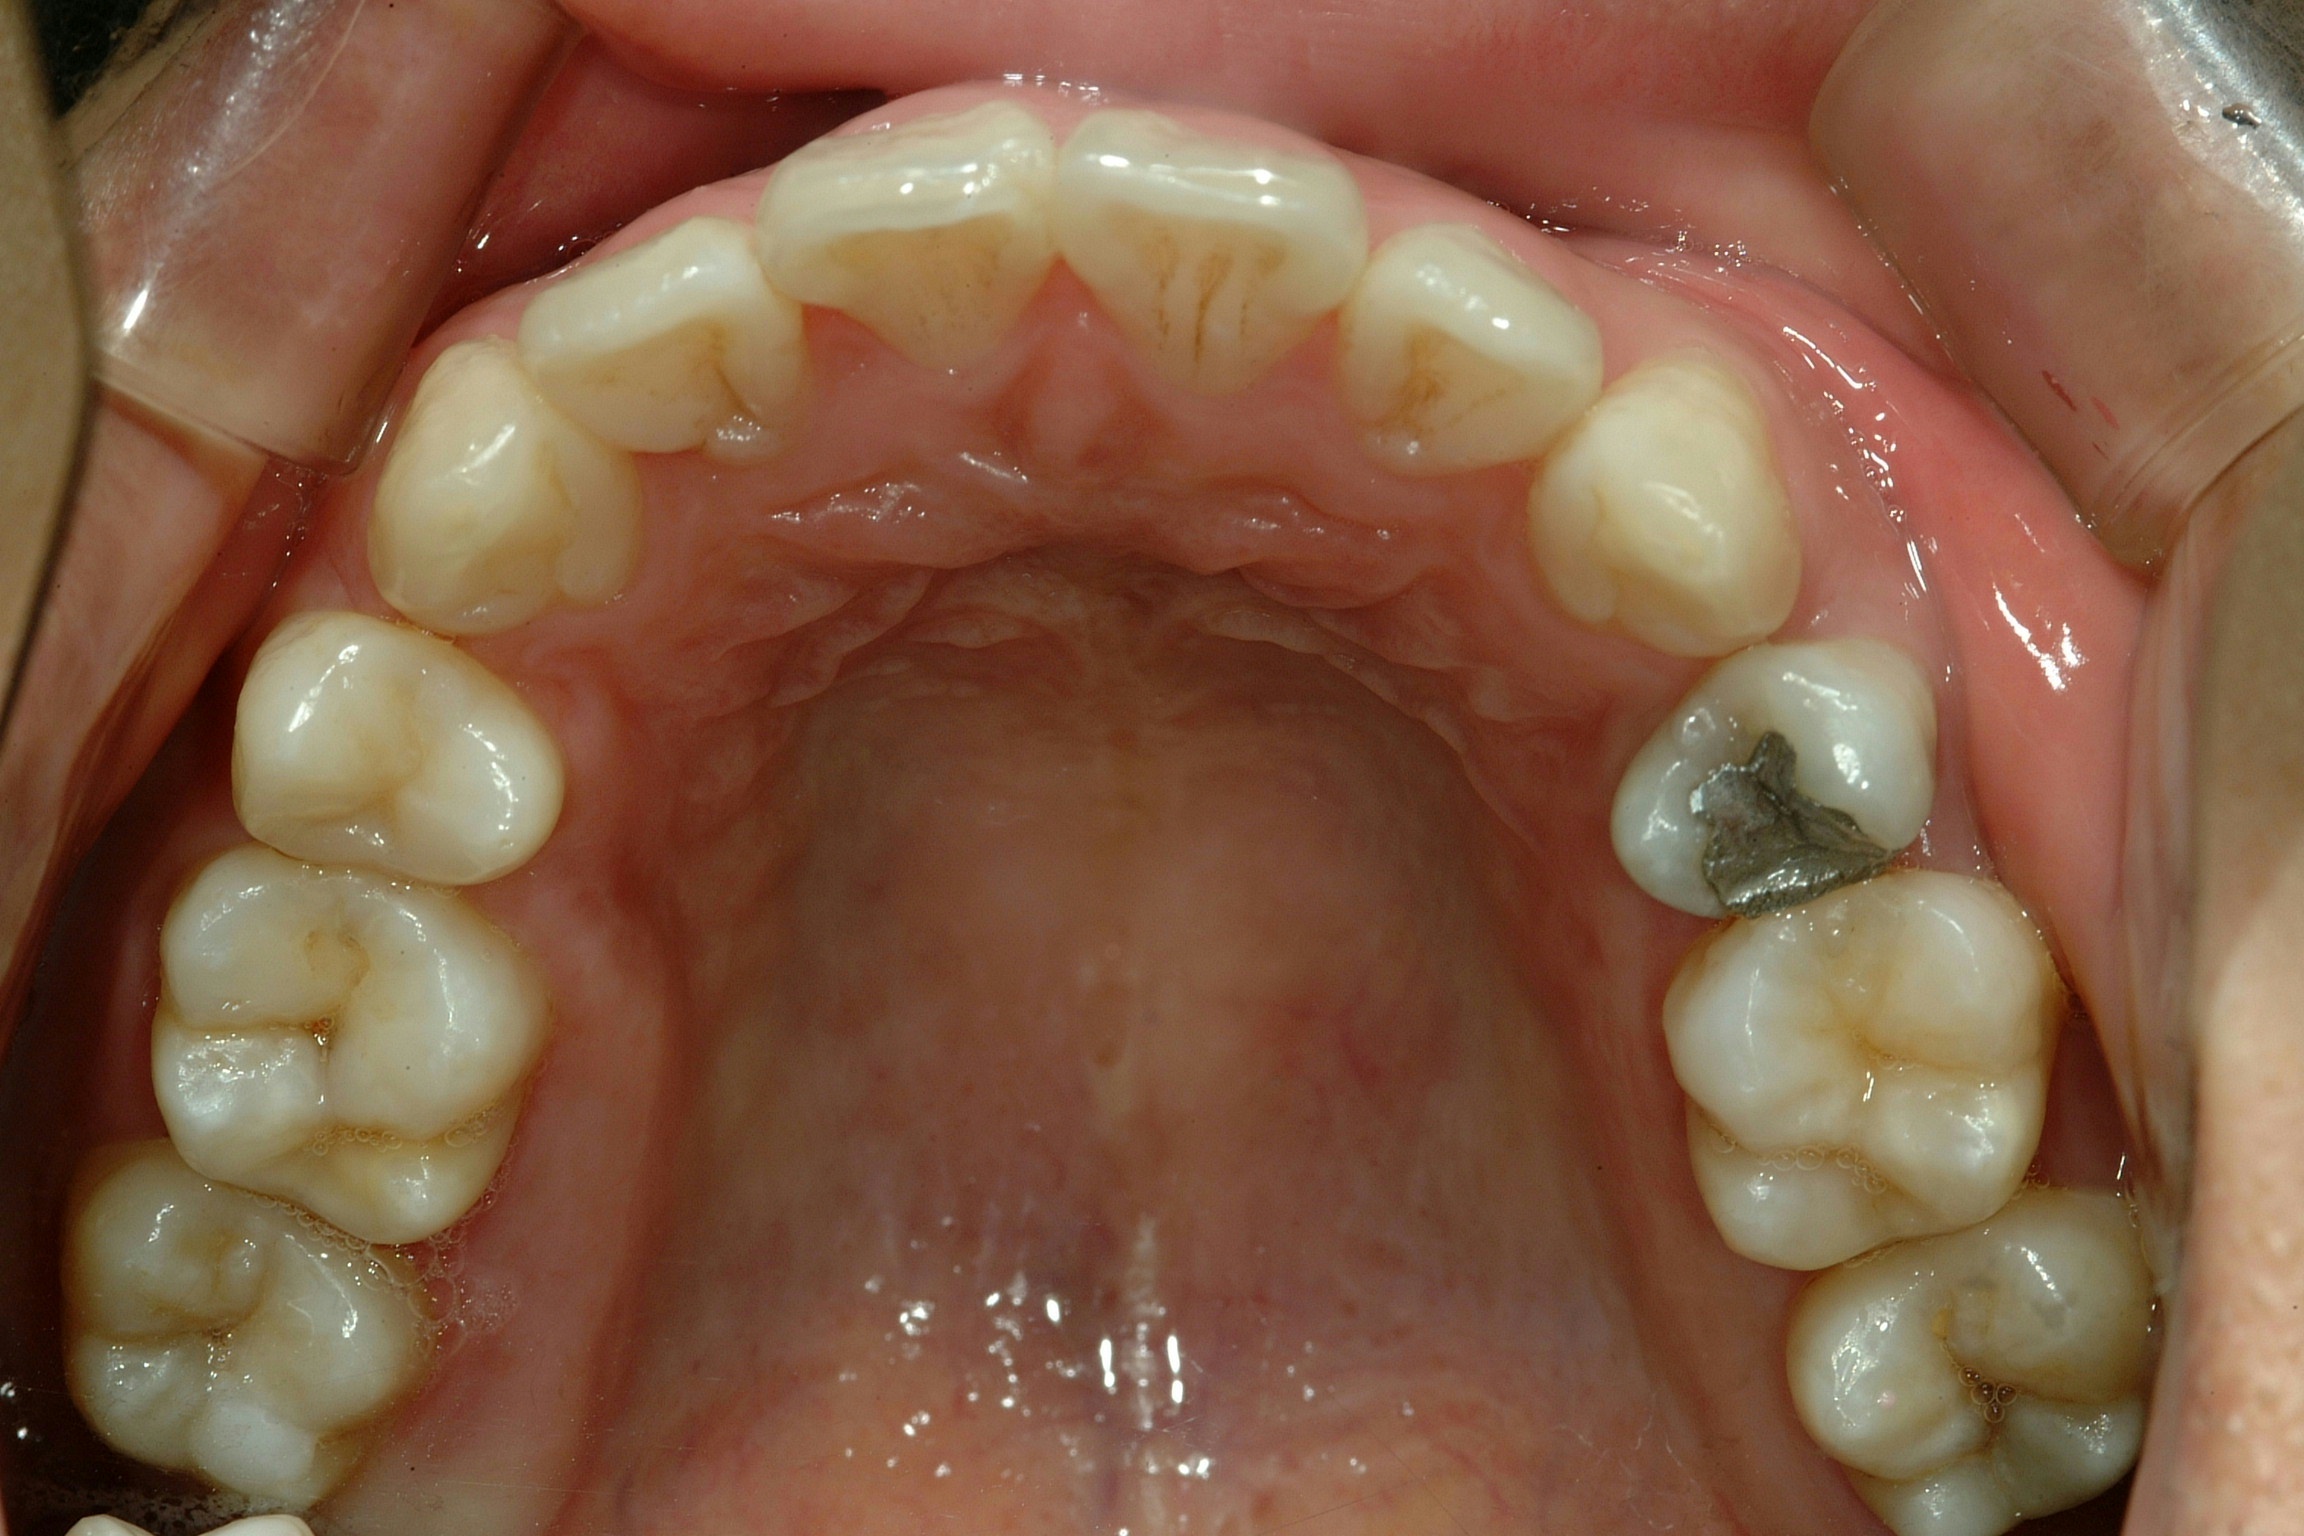

치료 후 사진입니다.